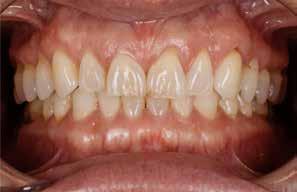

Den kliniske undersøgelse viser ingen symptomer fra muskler eller kæbeled. Ingen ledlyde ved åbne-/lukkebevægelse og ingen udsving ved åbne-/lukkebevægelse. Der er vertikalt overbid (VOB) 3-4 mm, horisontalt overbid (HOB) 1 mm, Angle kl. I med retroklination af såvel over- som underkæbeincisiver

A. Ortodontisk behandling med intrusion og proklination af underkæbefronten er simuleret med visualisering af slutresultatet. B-D. Nivellering af Spee kurve, type og position af attachments, biteramps på overkæbeincisiver til mild bidhævning, distorotation og distalisering af siderne i overkæben.

2. A. Orthodontic treatment with intrusion and proclination of the lower front simulated with visualisation. B-D. Leveling of the Spee curve, type and position of attachments, bite ramps on maxillary incisors for mild bite elevation, distorotation and distalization of the sides in the maxilla).

(Fig. 6 A-D). Relativt flad Spee kurve. Ud fra TWES 2.0 graduering har pt. slid af 2. grad i over- og underkæbefront, dog har 1-1 slid af 3. grad. Incisiverne har skarpe incisalkanter med emaljefrakturer og emaljeinfraktioner (Fig. 6 C, D) samt udtalte dentinkonkaviteter incisalt (Fig. 6 E). Posteriort ses slid af 1.-2. grad, og der er mistanke om natlig bruksisme, selvom patienten ikke oplyser dette. Der er såvel attrition som erosion med cuppings på flere molarer samt hævede fyldninger med mindre frakturer (Fig. 6 F, G). Erosiv årsag kan ikke identificeres ud fra kostanamnese. Der ses tydelige slidfacetter i hele tandsættet generelt. Patienten har perfekt mundhygiejne, ingen caries, slimhindeforandringer eller patologiske pocher.